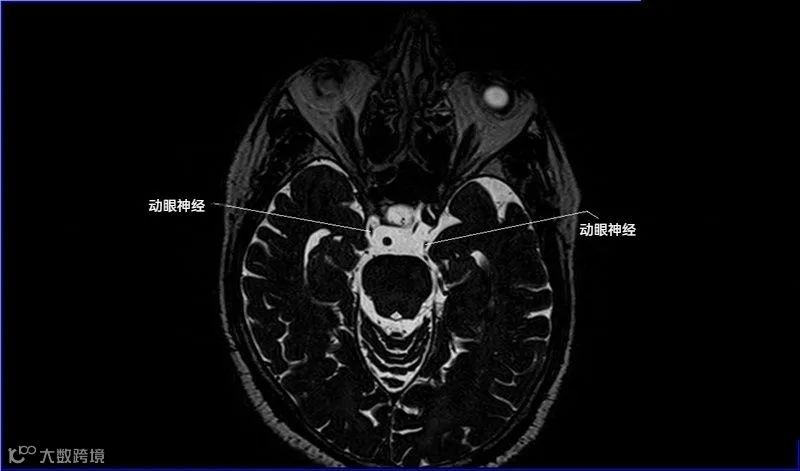

十二对脑神经口诀

一嗅二视三动眼,四滑五叉六外展,

七面八听九舌咽,迷走及副舌下全。